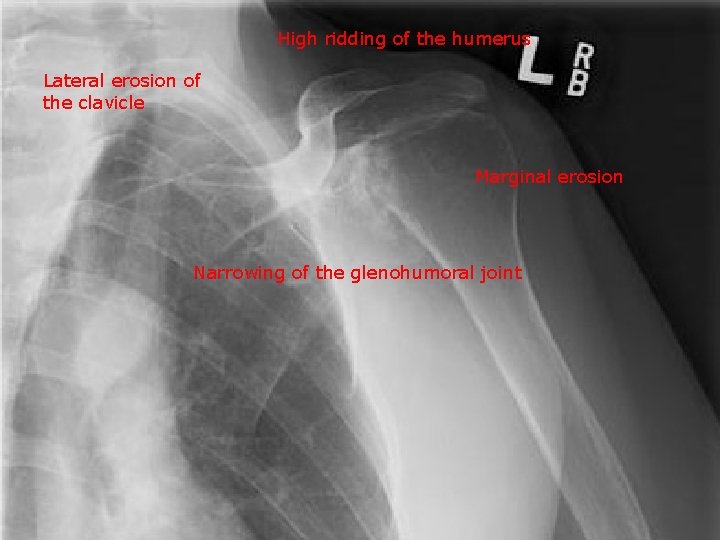

Rheumatoid arthritis :

Joint deformity Narrowing of the joint spaces Periarticular osteopenia Soft tissue swelling Joint instability due to ligament rupture Articular erosion

High ridding of the humerus Lateral erosion of the clavicle Marginal erosion Narrowing of the glenohumoral joint

Erosion of the lateral 3 rd of the clavicle is seen in the following: a. Rheumatoid arthritis b. Ankylosing spondylitis c. Langerhans cell histiocytosis d. Hypoparathyroidism (X ) Hyperparathyroidism e. Multiple myeloma (√ ) (X )